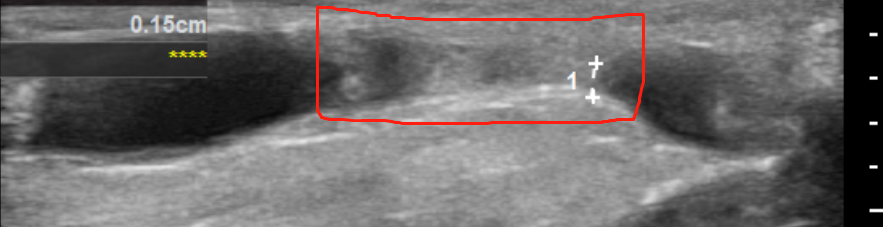

扩张前

扩张后